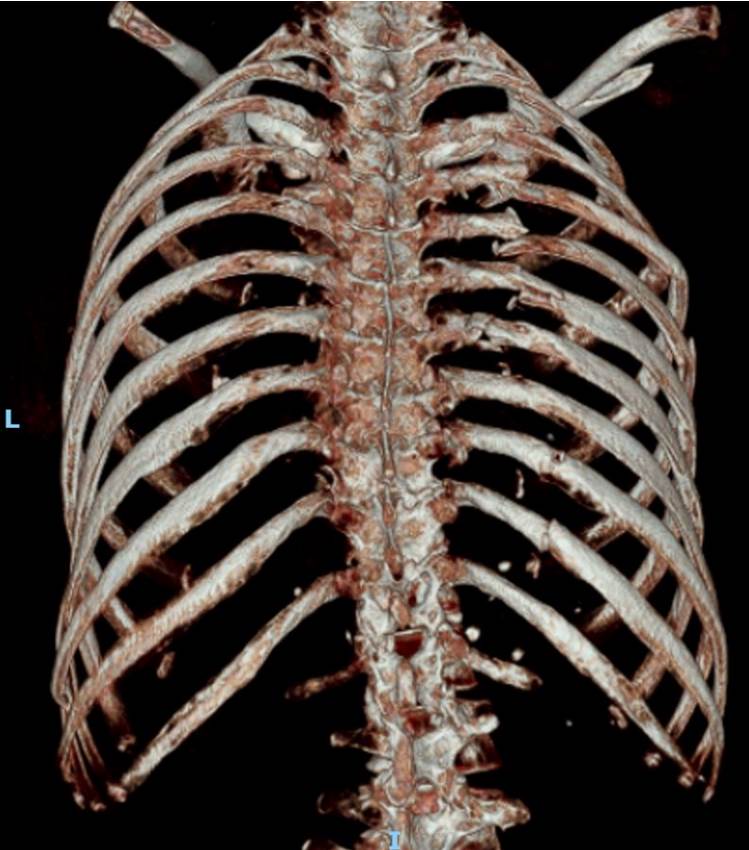

胸腔外科主任林聿騰表示,黃婦光肋骨就斷了21處,血胸、氣胸及胸廓變形,造成嚴重錯位的「連枷胸」,也就是相鄰3根以上的肋骨骨折,恐引發肺炎、呼吸衰竭等併發癥,準備開胸手術時,出現延遲性小腸破裂,指的是小腸並未在第一時間破裂,只得緊急穩住病人呼吸,請外科醫師先進行小腸部分切除手術,再進行胸腔手術。

林聿騰指出,整個變形的胸腔透過3D胸廓重組影像定位後進行微創手術,以鈦合金骨板及骨釘進行肋骨固定,穩定整個胸腔,讓患者可以正常呼吸,再交由骨科手術。